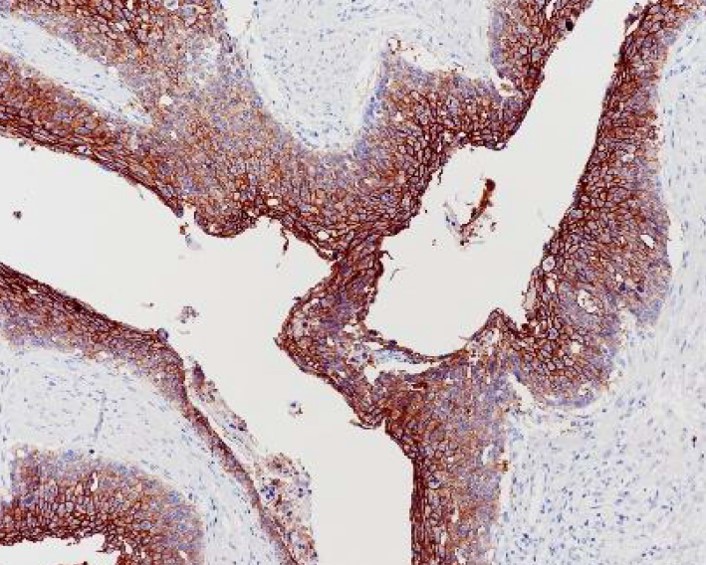

Trophoblast cell surface antigen 2 (TROP2), also known as tumor-associated calcium signal transducer 2 (TACSTD2), is an epithelial cell surface glycoprotein with low expression in normal tissues. In contrast, TROP2 is frequently overexpressed in a wide range of malignancies and is associated with poor prognosis and aggressive tumor behavior, including in triple-negative breast cancer (TNBC), non-small cell lung cancer (NSCLC), and pancreatic ductal adenocarcinoma (PDAC). These features make TROP2 a promising therapeutic target, driving the development of TROP2-targeted strategies such as monoclonal antibodies, antibody–drug conjugates (ADCs), and chimeric antigen receptor (CAR) T-cell therapies. arigo offers a specific TROP2 antibody to facilitate the detection of TROP2 expression in cancer tissues.

TROP2 antibody [SQab22266]